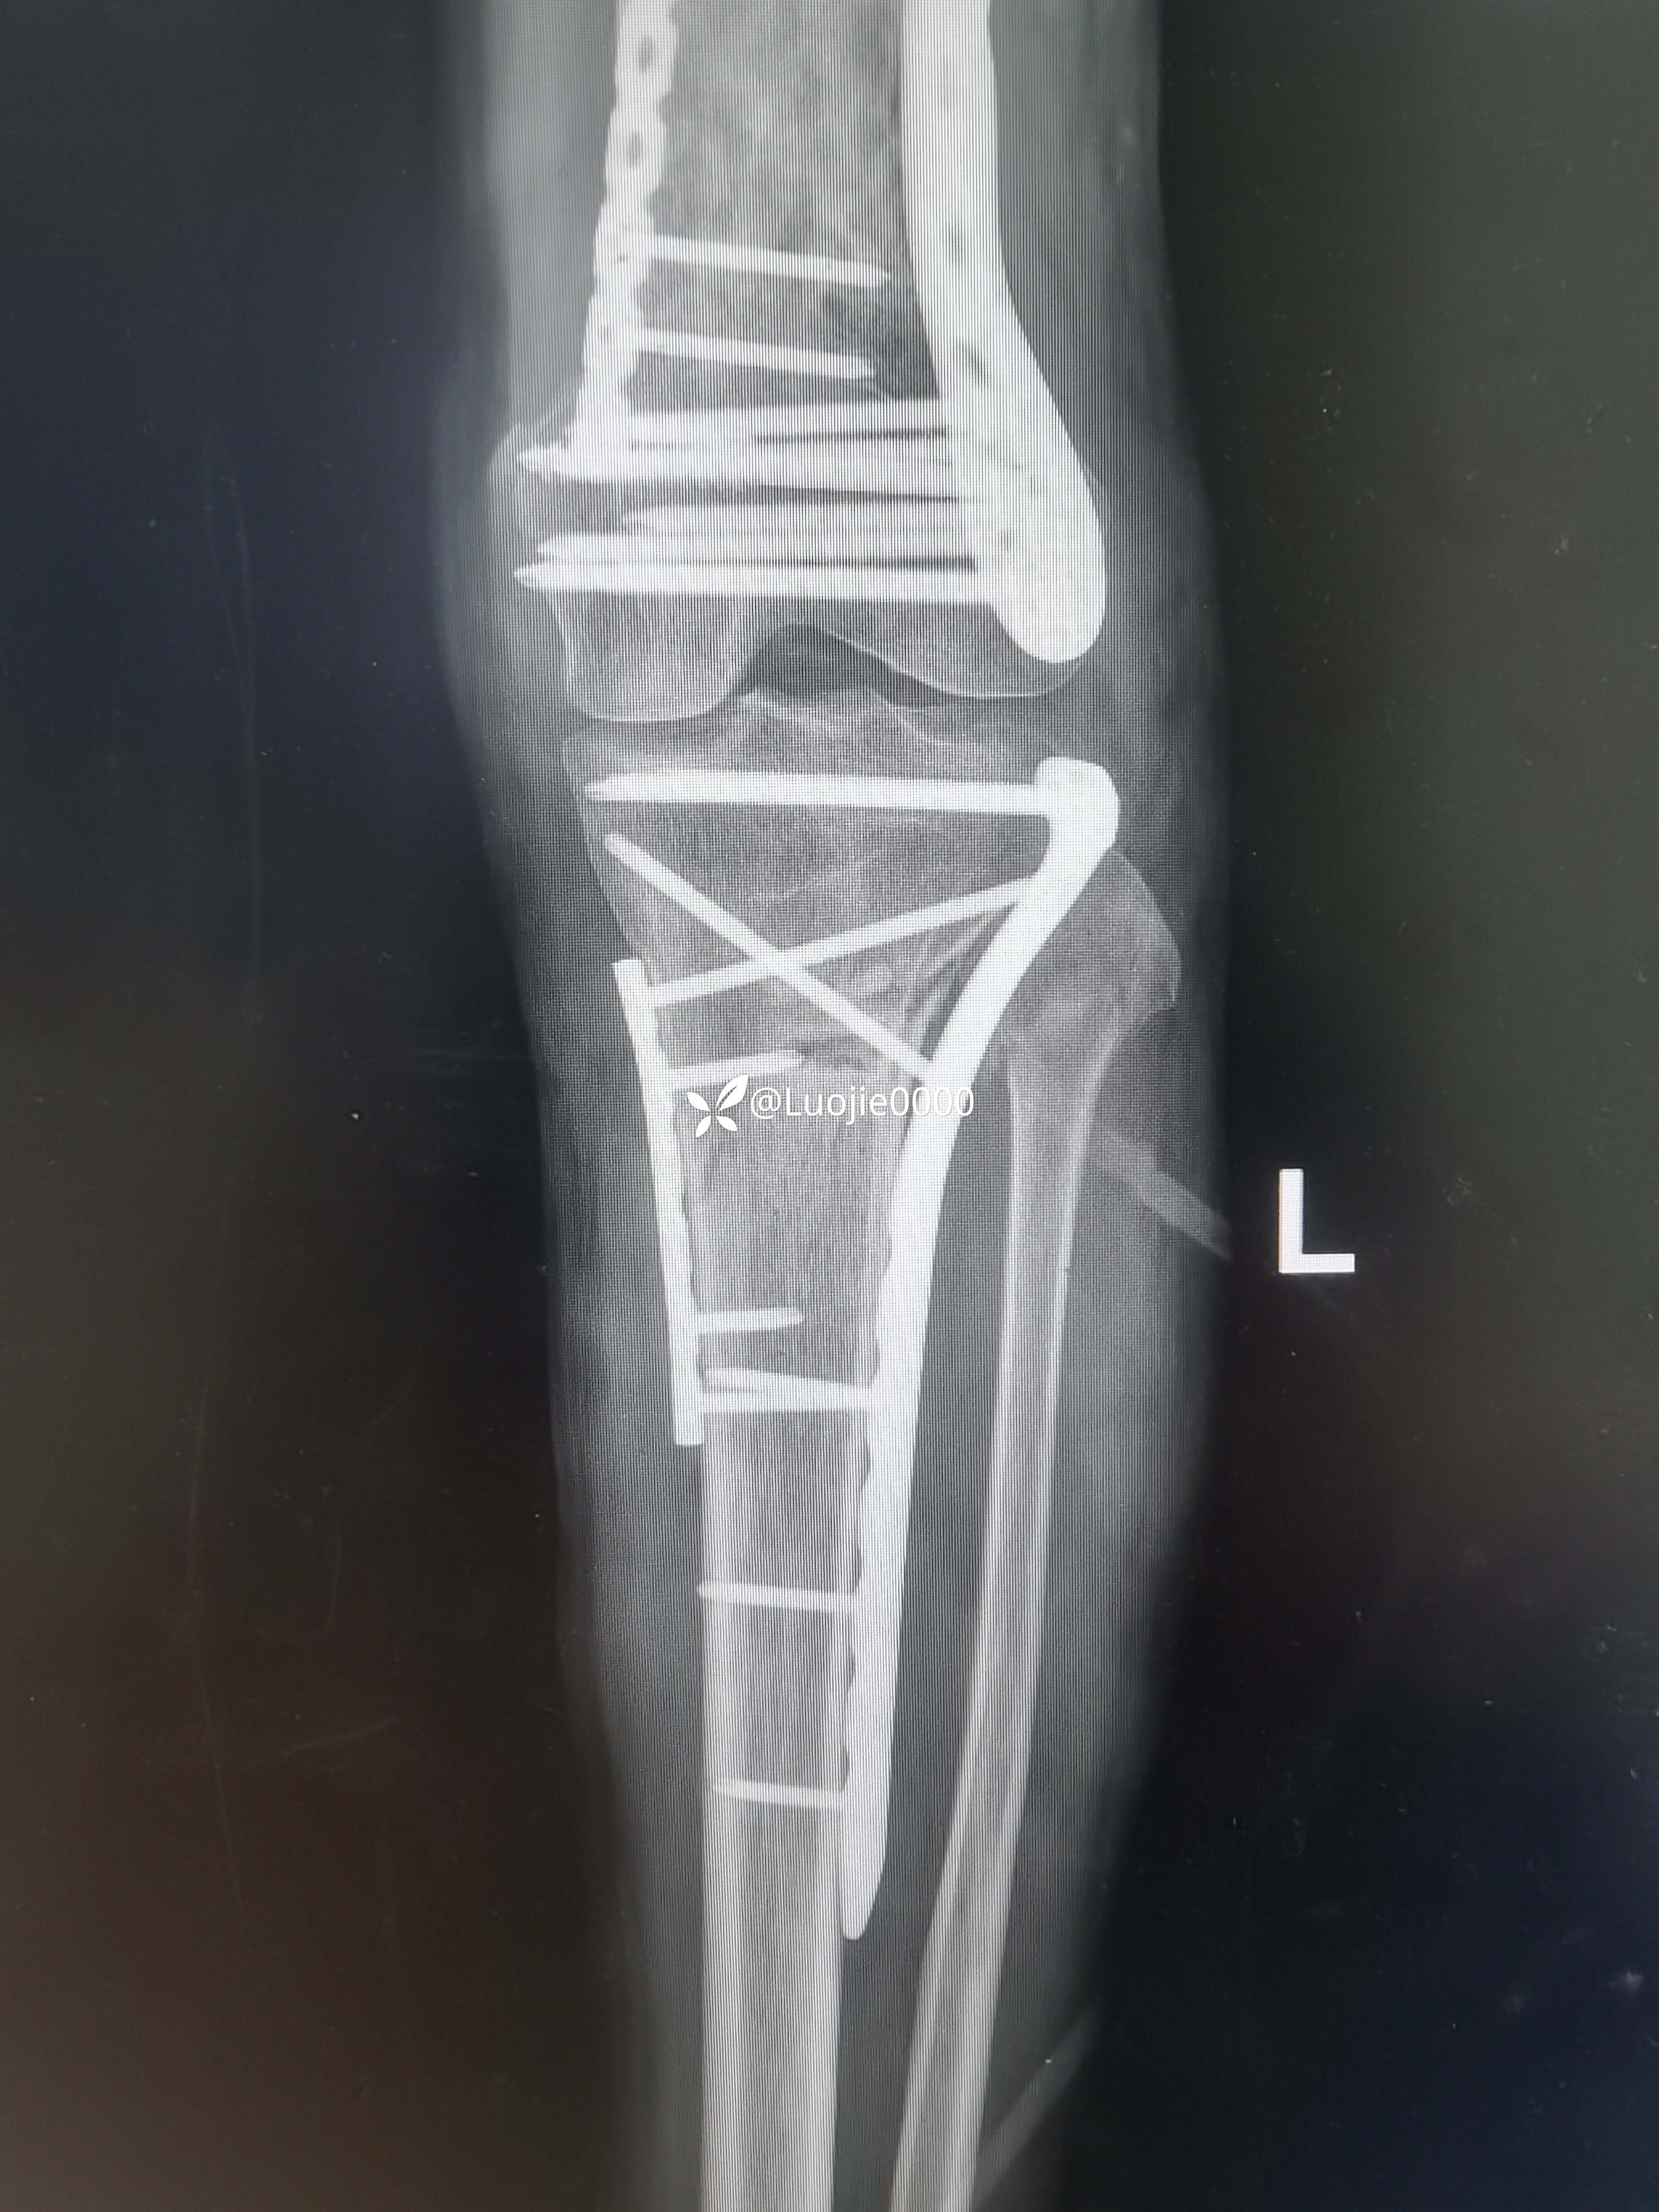

切开复的位

总结:1.理论指导临床,临床结合实际;

2.尽力把每一台手术做到极致 ;

3.合理运用好手中的工具。